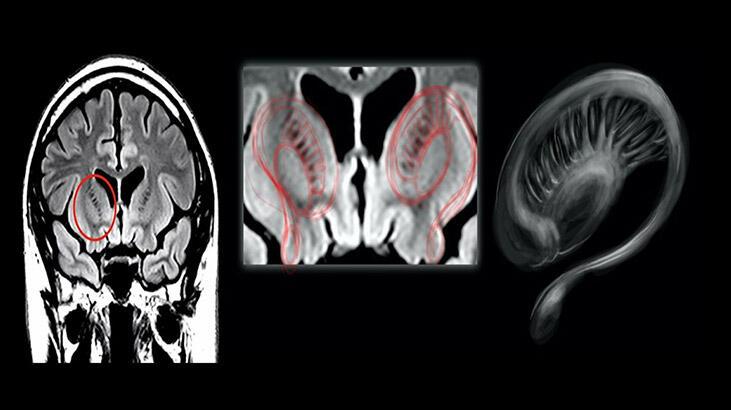

Muhabir Thobey Champion’ın isteği üzerine bu kişilerin MR görüntülerini tarif eden profesör, “Multipl skleroz hastası birinin MR’ına baktıysanız, beyaz cevher hastalığı denen bir şey görürsünüz. Yara izi vardır” ifadelerini kullandı:

MR boyunca dağılmış büyük beyaz bir leke veya birden fazla beyaz leke görürsünüz. Bu aslında bağışıklık sisteminin beyne saldırdığı ölü dokudur. Pilotların beyin görüntülerine en yakın durum buydu. Bir şeylerin yanlış olduğunu hızla görebilirsiniz.